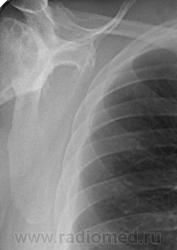

Пациент 60 лет, при прохождении проверочной флюорографии  обнаружены изменения со сторны плечевых суставов.Водитель троллейбуса.Страдает избыточной массой тела, люмбальгией, артороз коленных суставов.Непосредственно жалобы на плечевые суставы в медицинских документах не отражены. Какое будет мнение у коллег?

Пациент жалоб со сторны плечевых суставов не предъяляет и не помнит что бы когда- то что то беспокоило.Данных за сирингомиелию нет.

Александр, конечно надо доснять плечевые суставы... Из того, что есть: видимые отделы плечевых костей выглядят довольно симметрично, хотя слева и похуже, думаю - артроз. Весьма настораживает левая лопатка на предмет хондросаркомы

Снимки плечевых суставов.

Уважаемый Александр, приходиться признать, что на цифровой рентгенограмме легких изменения плечевых суставов видны лучше, чем на "обрезаных" и недоэкспонированых снимках суставов. По имеющимся данным могу только сказать, что деф. артроз с кистовидной перестройкой структуры есть. Под хрящевой опухолью (возможно - хондросаркома) левой лопатки я имела в виду тень, отмеченую красными стрелками, которая в поле снимка не вошла. Моя вина - в силу специфики работы такие узкоформатные снимки давно были вредными, т.к. очень часто патология остается за пределами снимка. Остается рекомендовать рентгенография левой лопатки в прямой передне-задней и косой проекциях, а лучше - КТ...